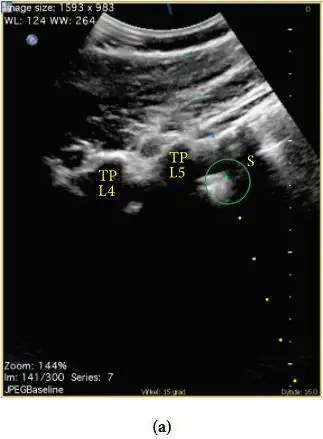

图2 腰骶隧道长轴超声图像